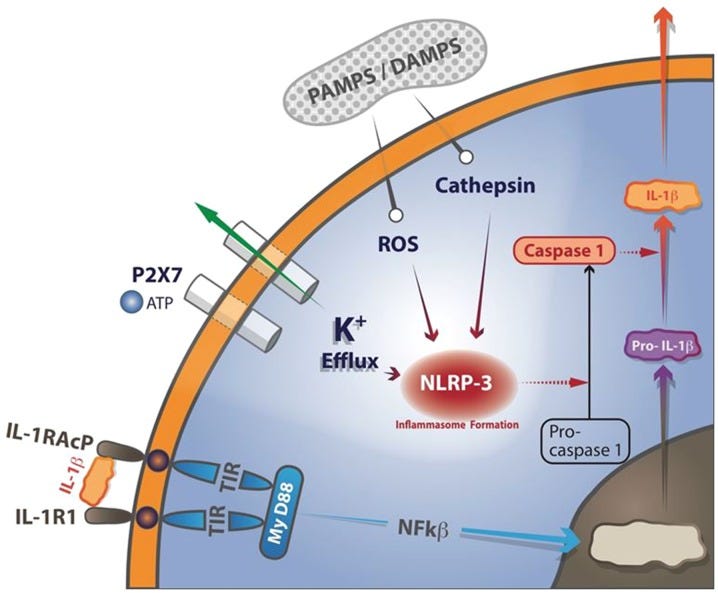

Endotoxin causes expression of IL-1β, which catalyzes expression of itself by initiating a Positive Feedback Loop.12

IL-1β binds to the IL-1 receptor type 1 (IL-1R1). Then the co-receptor chain, termed the accessory protein (IL-1RAcP), is recruited. This triple complex recruits the adaptor protein MyD88 to the Toll-IL-1 receptor (TIR) domain. Several kinases are phosphorylated, nuclear factor-κB (NF-κB) translocates to the nucleus, and pro-ILβ transcription ensues. The NLRP3-inflammasome is a cytosolic molecular structure composed of an adaptor protein, pro-caspase 1, and the NLRP3 sensor molecule, which may be activated by both infectious stimuli, known as pathogen-associated molecular patterns (PAMPs) and sterile stimuli, known as damage-associated molecular patterns (DAMPs). This activation is based on either ATP binding to the P2X7 receptor with a secondary efflux of potassium to the extracellular space or reactive oxygen species (ROS) formation. Upon activation of the NLRP3-inflammasome, pro-caspase-1 is converted to an active enzyme. Active caspase-1 then cleaves the IL-1 precursor in specialized secretory lysosomes or in the cytosol, followed by secretion of “mature” IL-1β.